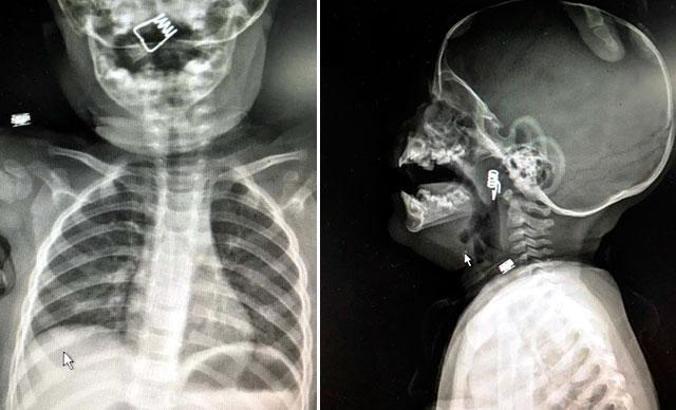

Nevşehir'de 1 yaşındaki erkek bebek Ö.Y., dün akşam saatlerinde elinde mandalla oynarken, parçalanan mandalın yayını ağzına aldı. Duruma müdahale eden bebeğin babası, yayı çocuğunun ağzından çıkarmaya çalışırken, yay bebeğin genzine kaçarak saplandı. Nevşehir Devlet Hastanesi Acil Polikliniği'ne getirilen bebeği, Acil Nöbetçi doktoru Mustafa Alpaslan muayene ederek gerekli tetkikleri yaptı. Çekilen röntgen filmlerinde mandal yayının lokalizasyonu ve durumu belirlendi. Daha sonra, KBB Uzmanı Op. Dr. Ahmet Cevatzade tarafından yapılan başarılı ameliyat sonucunda bebeğin genzine saplanan mandal yayı çıkartıldı.

Operasyonu gerçekleştiren Dr. Cevatzade, ''Özellikle 1-12 aylık döneme karşılık gelen süt

çocuğu döneminde bebekler her şeyi ağzına alır. Üzerinde 3 yaş altında kullanılmaması gerektiği yazan ürünlere karşı bazen anne ve babalar pek dikkatli davranmayabiliyor. Bu tarz ürünler boğaza kaçabiliyor. Bu konuda ailelerin küçük çocuklar için yabancı cisim aspirasyonlarına dikkat etmeleri gerekiyor. Nefes borularına kaçacak parçaları uzak tutmaları gerekiyor. Ayrıca 3 yaş altı çocuklarda çerez gibi küçük parçacıklı maddeleri vermemeleri de gerekir. Ağızdan alınan her türlü yabancı cisim hava yolunu tıkadığında hayati tehlike oluşturur'' dedi.